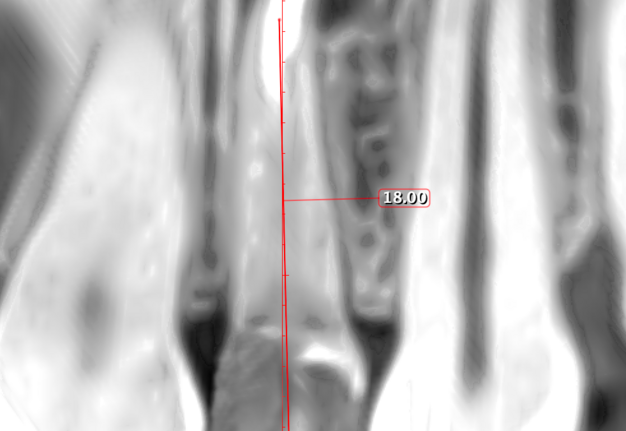

Therefore, the selection of this type of incision requires thorough treatment planning [12]. To avoid the incision falling into an existing bone defect or a defect created by an osteotomy, it is rational to plan a submarginal incision. We can determine whether we can make it, according to the clinical situation of a patient by following approach. To do this, first we need to determine on the CBCT where the bone defect is located or where the osteotomy will take place. Then, using a virtual ruler, measure the distance from the incisal edge of the tooth on which the intervention will be performed to the beginning of the bone defect or osteotomy (Fig 7).

We transfer this distance is transferred to a metal probe and fixed with an endodontic stopper. Next, we take a plastic probe and substitute it near the zenith of a tooth on which the intervention will be performed at a mark of 6 mm (3 mm must be retreated to perform a submarginal incision and another 3 mm is needed for the formed flap to overlap healthy bone tissue) (Fig 8).

We compare the lengths of the plastic and metal probes. The first option is when the metal probe is above the plastic one, then we can assure that the incision and the Ochsenbein-Luebke flap will accurately cover the bone defect and the submarginal incision is safe (Fig 9).

The second option is when the lengths of both probes are the same. This option is when a tooth has previously undergone root apex resection or a root is anatomically short or there is extensive periapical lesion. Under these conditions, we understand that there is still a safe distance of 3 mm so that the formed Ochsenbein-Luebke flap will also cover the bone defect and therefore, we can perform a submarginal incision and flap (Figs 10 and 11).

The third option is when the length of the metal probe is shorter than the plastic one. This option arises when the tooth has root resorption, root perforation or extensive periapical lesion extending to the alveolar crestal bone. In such conditions, performing a submarginal incision is contraindicated and it is preferable to use a papilla-base or intrasulcular incision (Figs 12 and 13).